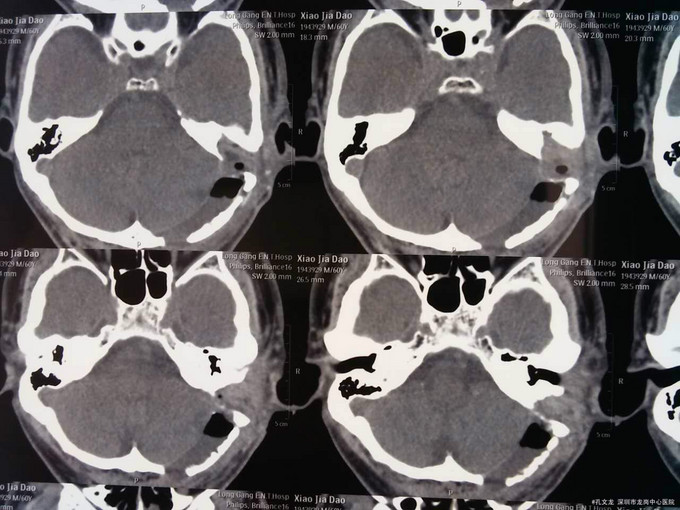

诊断:自发性颅内积气(张力性) 入院后予以完善相关检查,行颞骨乳突薄层CT扫面,考虑乳突气房内耳道漏气,粘膜瓣形成张力性气颅,再次开路手术创伤大,联合耳鼻喉科,行颅外手术,耳后入路磨除乳突气房,发现粘膜活瓣样活动,分辨漏气口,自取皮下筋膜,及带蒂肌皮瓣,填塞漏口及乳突气房,生物胶粘合,手术顺利,术后恢复良好。